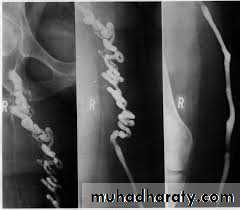

Angiography of buerger disease ((corkscrew))